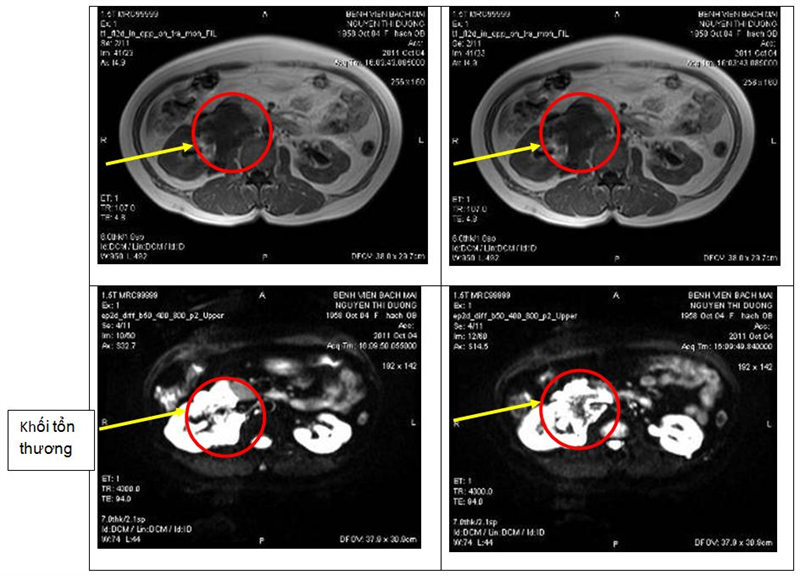

Trước khi quyết định sinh thiết, các chuyên gia chẩn đoán hình ảnh đã xem xét lại và quyết định chụp cộng hưởng từ ổ bụng để đánh giá lại. Bệnh nhân được chụp cộng hưởng từ ngày 6/10/2011. Kết quả: Hình ảnh khối lớn có tính chất dịch ôm quanh rốn thận phải và ôm quanh tĩnh mạch chủ dưới kích thước khoảng 10cm, nghĩ tới u bạch mạch lành tính